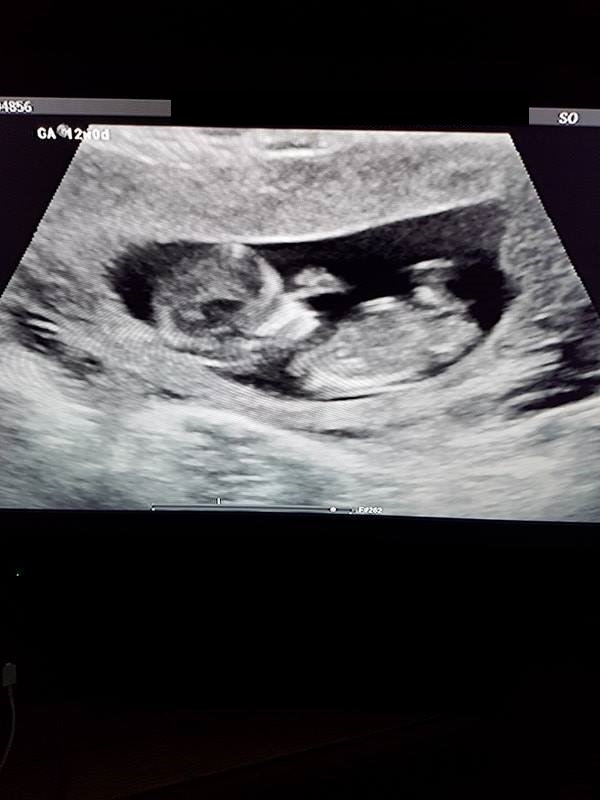

Hi! Just wondering if there is a nub in these photos, and if so, if you would guess it's a boy or girl? 12+0 weeks. Thank you!Attachment 38349Attachment 38350Attachment 38351Attachment 38352Attachment 38353